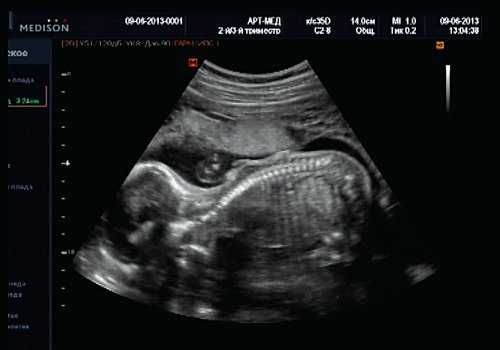

При эхокардиографии изучались четырехкамерный срез сердца плода (рис. 1) и срез через три сосуда (рис. 2). УЗИ проводилось трансабдоминальным датчиком, лишь при необходимости (затрудненная визуализация) использовался внутриполостной датчик. Четырехкамерный срез сердца плода при ультразвуковом сканировании трансабдоминальным датчиком визуализировался в 85% случаев, срез через сосуды - в 73%, при использовании трансвагинального датчика эти цифры существенно возрастали до 100 и 91% соответственно. Оптимизация пренатальной диагностики ВПС может быть достигнута путем строгого соблюдения основных методических правил. При оценке четырехкамерного среза плода необходимо оценить нормальное расположение сердца плода, исключив его эктопию (рис. 3), положение оси сердца плода, что не представляет никаких трудностей, нормальные пропорции и размеры камер сердца, движение створок атриовентрикулярных клапанов должно быть свободным, септальная створка трикуспидального клапана должна располагаться ближе к верхушке сердца (рис. 4). При оценке среза через три сосуда необходимо оценить взаиморасположение сосудов и их диаметр.

Рис. 1. Беременность 12 недель. Четырехкамерный срез сердца плода. Отчетливо видны камеры сердца.